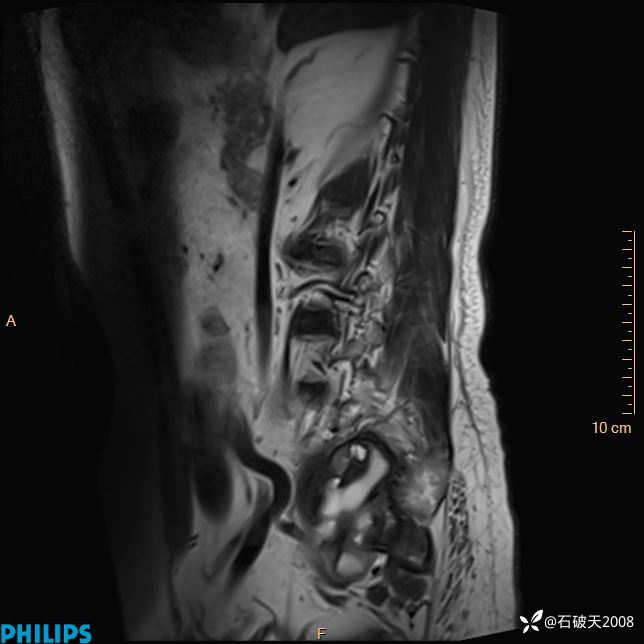

2023年3月份MRI影像

T1矢状位